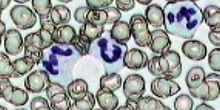

Práctica de Frotis sanguíneo